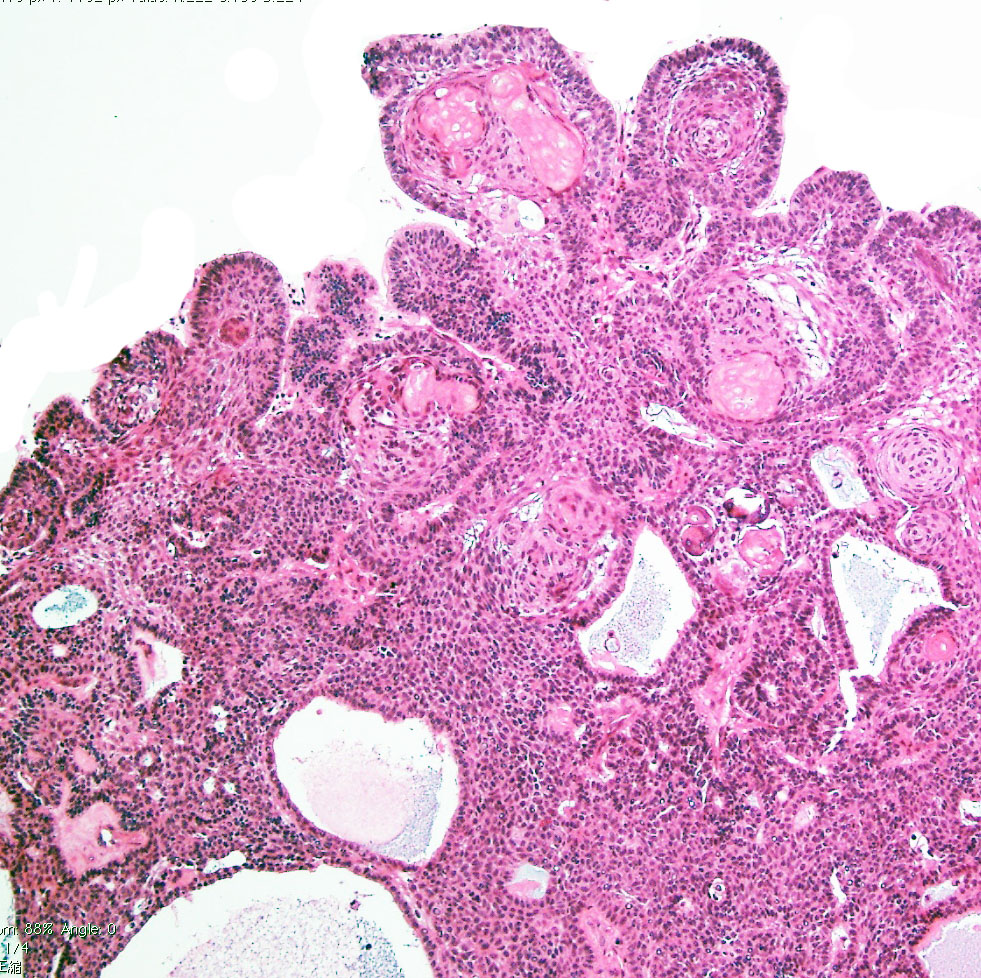

視床下部浸潤(よくあることで重要)

Adamantinomatous craniopharyngioma invading brain tissue. This type of hypothalamic invasion is frequently seen in the suprasellar/ intraventricular craniopharyngioma.

The border between tumor cells forming lateral palisading (center) and hypothalamic glial tissue (upper right) is not clear. There is no cleavage plane.

adamantinomatous typeのfinger-like protrusion

Adamantinomatous craniopharyngioma showing surface finger (tongue)-like protrusion contains small cysts, wet keratin, and stellate reticulum.